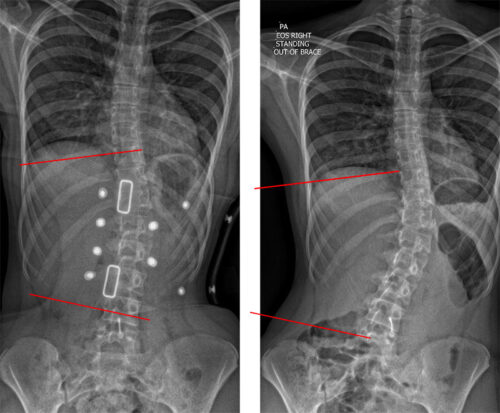

التشخيص المبكر هو الخطوة الأهم لتحديد ما إذا كان الاعوجاج عرضًا لحالة صحية أخرى. يعتمد التشخيص على:

الفحص السريري

يقوم الطبيب بملاحظة شكل الجسم ووضعية العمود الفقري.

فحص قوة العضلات وردود الفعل العصبية.

تحدد زاوية الانحناء وشكل الفقرات.

تساعد على اكتشاف الاعوجاج الخلقي أو أي تشوهات في العظام.

الفحوصات المتقدمة

مثل MRI أو CT scan إذا كانت هناك علامات على وجود مشاكل عصبية أو أورام.